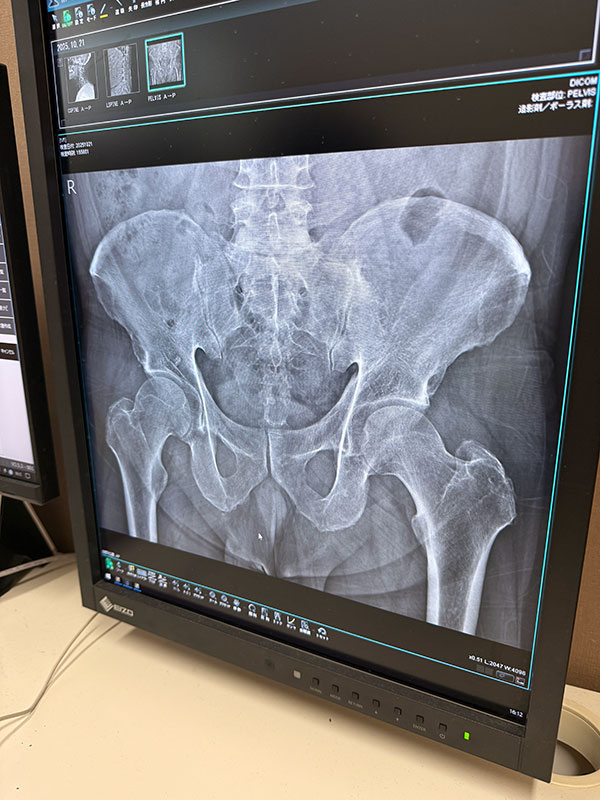

| 2025/10/21火 楓の森で検査 ↓前 次↑ 朝イチ女王送ってクルっとひさ枝へ。 ![]() 8:30ぐらいですが少し落ち着いてきたのかな。 ![]() 姉やんから頼まれたお土産うどん買いがてらでしたが久々釜玉かけを。うむ、自分にとってのこの店はやっぱこれやな。 ![]() 主治医モリケン先生のトコにも行きます。受付の美女に「いつもの膝ですか?」→「はい、それに加え腰と尻と首と。。」→「事故か何かで?」→「いや転んだと言うか。。」→「いつですか?→「10/18土です」てか 「先生も知ってますので」 ※その場にいたw というやりとりをしました!レントゲン撮ってもらいました。 ![]() ドキドキしながら結果を。 ![]() 首は一箇所狭まってるそうで、今回のが原因ではなく加齢とのこと。ヨシキよりかはマシでしょう。 ![]() ヒビ等はないようです。 ![]() 椎間板はもうすぐヘルニアかもやけど、それは元々やからなあ。 ![]() パイプ椅子で頭打ったけどそれなかったらもっとヤバかったかもとのことでした、ともかくHOTしつつ 正式に椅子アクションを禁止 ※ジャンプもデス されました。新しい面白いコトを探しましょう。 ![]() いつもの膝ヒアルロン酸デュアル打ってもらって後に。 ![]() ひさ枝でもらった麺で寄せ鍋ですか。 ![]() 土曜のライブや日曜からの九州出張までに痛さマシになってて欲しい。 ↓前 次↑ | ||